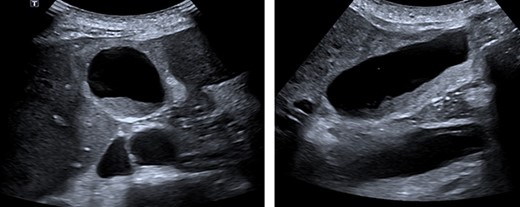

A 72-year-old male presented with a two-day history of right upper quadrant pain on a background of a metastatic, small bowel, well-differentiated NET diagnosed 5 years previously. The tumour was a low-grade mesenteric NET with a ki67 of 8% at diagnosis. He had multiple liver metastasis, which were stable. Carcinoid syndrome was well controlled on a long-acting, monthly dose of a somatostatin analogue with last dose being 28 days prior to presentation and due in three days. His comorbidities included hypertension, an infrarenal aortic aneurysm and chronic obstructive pulmonary disease. He presented with right upper quadrant tenderness and the liver edge was palpable 4 cm below the costal margin. Initial blood tests showed a white cell count of 18.9 × 109/L, C-reactive protein 212 mg/L and liver function tests within normal limits. Vital signs were reassuring, and an abdominal ultrasound described a thickened gallbladder wall, mobile sludge and an 8.5-mm common bile duct suggestive of cholecystitis (Figure 1). Computerised tomography (CT) of the abdomen was noted to show multiple segment V liver masses with capsular deformity suggestive of central necrosis. He was initially managed with analgesia and intravenous piperacillin-tazobactam. After a discussion with the patient and consultation with his treating oncologist regarding his relatively stable disease burden and reasonable prognosis, a laparoscopic cholecystectomy was performed.

Abdominal ultrasound. A layer of mobile sludge and thickened gallbladder walls. Several liver lesions with mixed echogenicity were noted, several adjacent to the gallbladder fossa.